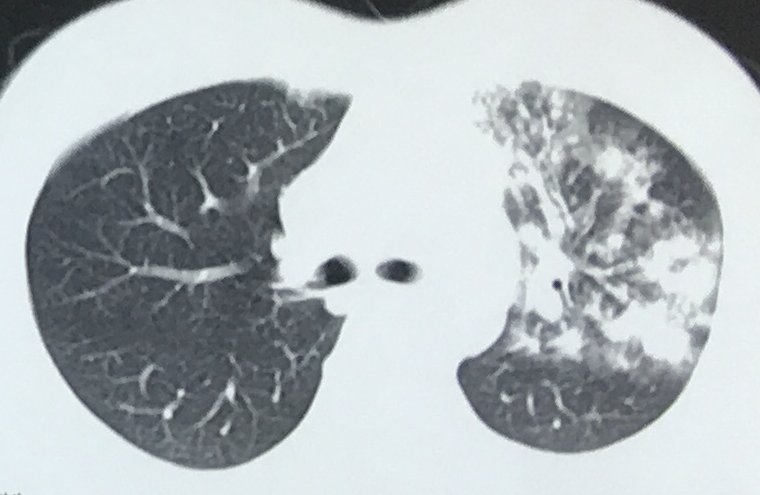

2. 血行播散性肺结核:急性血行播散性肺结核表现为两肺均匀分布的大小、密度一致的粟粒阴影;亚急性或慢性血行播散性肺结核的弥漫病灶,多分布于两肺的上中部,大小不一,密度不等,可有融合。需与电焊工尘肺、肺转移瘤等其他疾病鉴别。

*血行播散性肺结核:均匀分布的大小、密度一致的粟粒结节

*误诊为血播肺结核的电焊工尘肺,弥漫性肺病都必须询问职业史,无发热的血行播散性肺结核诊断需谨慎

*甲状腺癌肺转移:27 岁女性,双肺弥漫性粟粒影,误诊为血播,因无发热,质疑诊断,最后确诊为甲状腺癌肺转移。